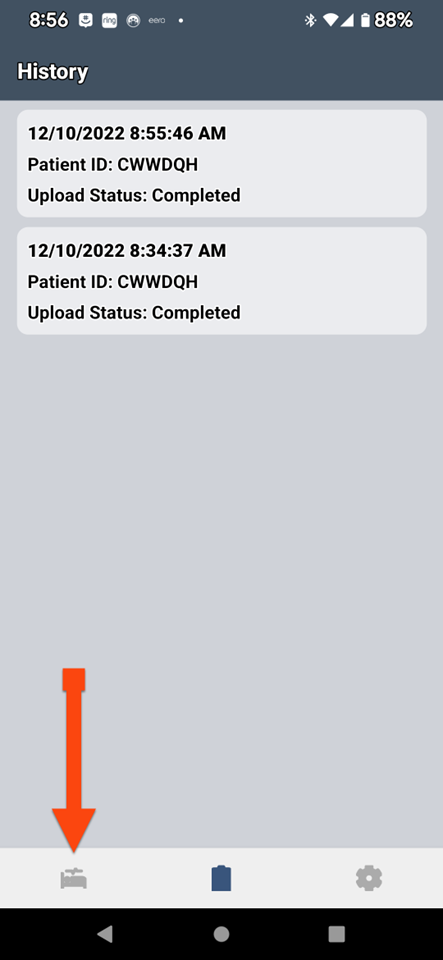

SLEEPIMAGE APP (Android)

SLEEPIMAGE APP (Android)

SLEEPIMAGE APP (Android)

SLEEPIMAGE APP (Android)

SLEEPIMAGE APP (Android)

SLEEPIMAGE APP (Android)

SLEEPIMAGE APP (Android)

SLEEPIMAGE APP (Android)

SLEEPIMAGE APP (Android)

SLEEPIMAGE APP (Android)

SLEEPIMAGE APP (Android)

SLEEPIMAGE APP (Android)

SLEEPIMAGE APP (Android)

SLEEPIMAGE APP (Android)

SLEEPIMAGE APP (Android)

SLEEPIMAGE APP (Android)

SLEEPIMAGE APP (Android)

SLEEPIMAGE APP (Android)

SLEEPIMAGE APP (Android)

SLEEPIMAGE APP (Android)

SLEEPIMAGE APP (Android)

SLEEPIMAGE APP (Android)

SLEEPIMAGE APP (Android)

SLEEPIMAGE APP (Android)

SLEEPIMAGE APP (Android)

SLEEPIMAGE APP (Android)

SLEEPIMAGE APP (Android)

SLEEPIMAGE APP (Android)

SLEEPIMAGE APP (Android)